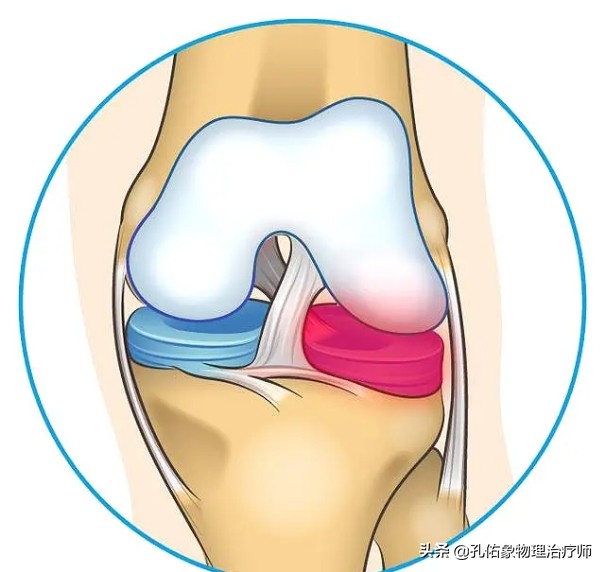

首先,半月板的愈合能力决定因素是它的血供,因为半月板的血供非常差,一旦半月板发生撕裂,要想通过保守来自我愈合,这种愈合的可能性不大。因为半月板的血供有这样的一个特点:

仅仅是在靠近膝关节的关节囊外层区域有一定的血供,临床上称此区域为红区;而在半月板最内层区域,是没有血液供应的,仅仅靠滑液来供应营养,临床上称此区域为白区,若是损伤了,基本不可能自愈;在红区与白区之间的这个范围,称为红白区,血液供应也不太多,自愈恢复相对较慢。对于老年人来说,因为自身的血液循环相对不好,若是出现半月板的白区及红白区的损伤,愈合能力就非常低。所以,半月板的损伤,一般都还是建议手术治疗。

- 半月板的缝合术

这种手术方式往往适用于损伤部位在红区的患者,如上图中标记1和2的部位损伤者;由于这个区域的半月板有血供,都会选择半月板缝合的方式来让它自愈,为减少后期的并发症(如创伤性关节炎、活动时的卡顿等)埋下伏笔。

- 半月板的部分切除成型术

这种手术方式往往适用于损伤部位在红白区的患者,如上图中标记3和4的部位损伤者;由于这个区域的半月板虽然仍有部分血供,但是相对红区的愈合能力就大大的降低,所以一般会选择半月板的部分切除成型的方式来弥补半月板的形状,为减少后期的并发症(半月板的磨损)埋下伏笔。这个手术的特点就是把损伤撕裂的半月板切除,然后尽可能的恢复还原半月板的C型或O型的形态结构。